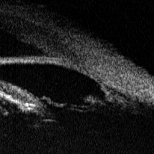

Ультразвуковая биомикроскоиия - это новый метод

В-сканирования. в котором применяются высокие частоты в диапазоне 50-100 М Гц.

При этом глубина проникновения составляет 5-7 мм. этот метод позволяет получить

изображение структур переднего сегмента глаза с высоким разрешением и полезен

для определения механизма вторичной глаукомы (рис. 1). [2].

Рис. 1 - Ультразвуковая биомикроскопическая

картина структур угла передней камеры